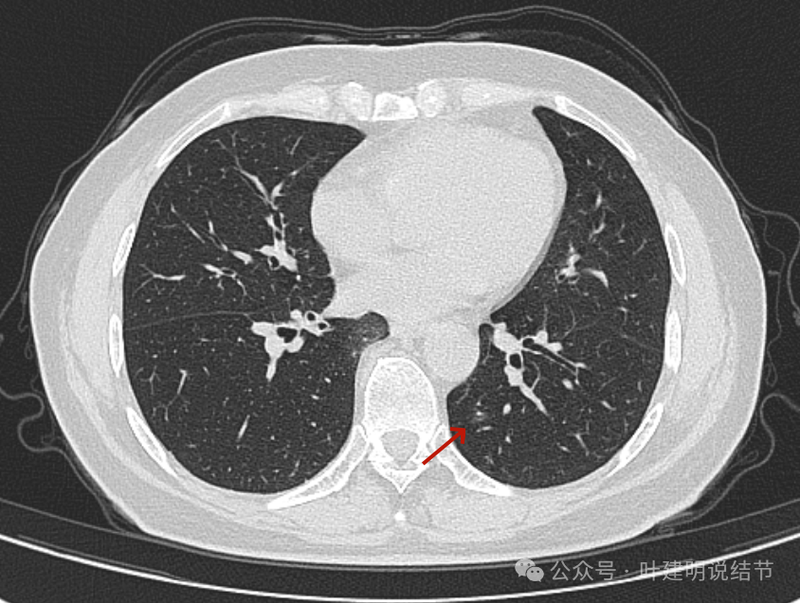

病灶出现,磨玻璃密度,略有偏实性成分,整体轮廓与边界较为清楚。

混合密度,轮廓清。有实性成分、有局部细支气管扩张、有浅分叶征,病灶有明显磨玻璃成分。

灶内细支气管扩张、边缘毛刺、虽小却有明显分叶征、整体轮廓与边界清楚、实性成分明显。

细支气管扩张以及边缘细毛刺,整体轮廓清。

磨玻璃密度伴少许偏实性成分,有微小血管进入。

边缘区密度淡,但轮廓仍清。